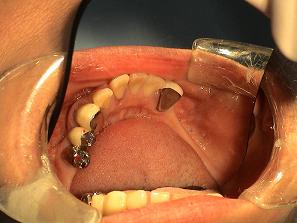

3.

バネなし入れ歯を入れた

状態です!!

* 金属のバネがないので

見栄えが良いです!

入れ歯が入っているとは

気がつかれにくいです!!